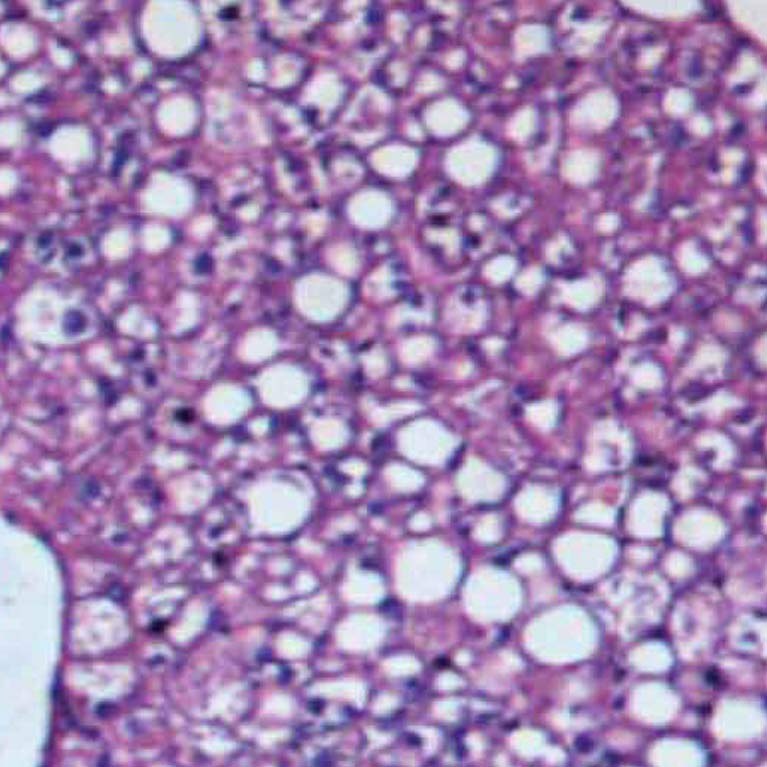

Salk scientists study the many molecular processes used by the body to convert food into energy. They want to understand how these systems—known collectively as metabolism—develop and how they go awry in conditions such as diabetes and obesity. Ultimately, this information might be used to develop new ways to prevent and treat these conditions.